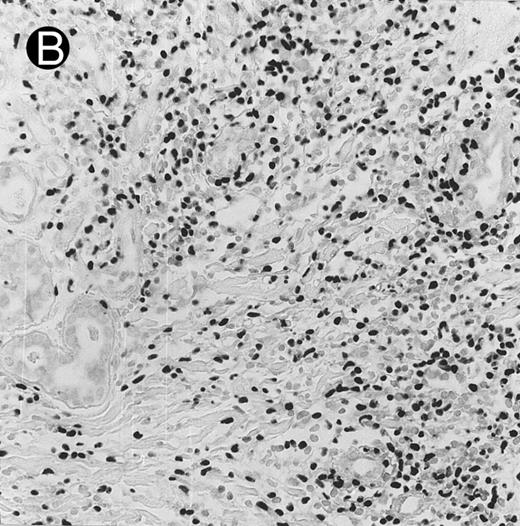

Cutaneous nasal-type NK/T-cell lymphoma (case no. 34). (A) This biopsy was initially misinterpreted as vasculitic lesion because of the small size of the lymphoid cells and the minimal cellular atypia. (B) Large numbers of lymphoid cells in the skin show positive labeling for EBERs on in situ hybridization. The sweat gland in the left field is negative.

By definition, the neoplastic cells showed CD56 expression (Fig 4). All except 2 cases (cases no. 7 and 12) reacted with the polyclonal CD3ε antibody on paraffin sections, but both CD3ε− cases were immunoreactive for CD43 and CD45RO. Among 18 cases in which frozen tissue was available for analysis, all were CD2+; 1 case each stained for CD3/Leu4 (weak staining), CD7, and CD8 and all cases were negative for CD4, CD5, CD16, CD57, and B-lineage markers. Thirty-two (94.1%) cases showed labeling for EBERs in practically all neoplastic cells (Fig 3B); 2 cases were negative.